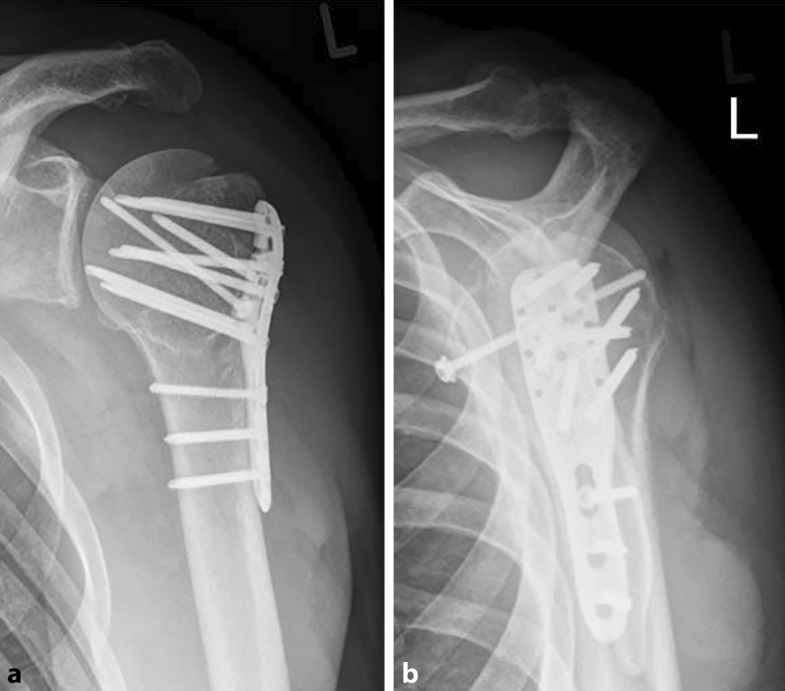

From link.springer.com

Headsplit fractures of the proximal humerus SpringerLink Split Cast Fracture This article explains what to expect while you are wearing your cast or splint and. However, they differ in their. casts and splints hold broken bones in place while they heal. casts are most commonly used to hold a part of your body in place while you’re healing after a bone fracture (a broken bone). It is important. Split Cast Fracture.

Headsplit fractures of the proximal humerus SpringerLink Split Cast Fracture 1 immediate management of these injuries includes applying a plaster cast—called a back slab—to the dorsal aspect of the forearm. The sides of the bivalve cast will be taped with cloth. you have been fitted with a cast or splint to protect your bone and reduce pain as you heal. casts are most commonly used to hold a. Split Cast Fracture.